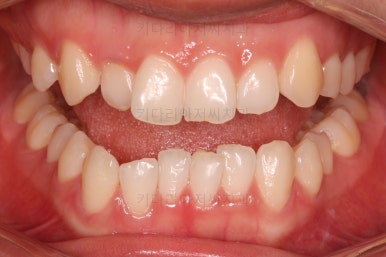

점점 가지런해지고 있네요.

치료가 1년만에 종료가 되었네요.

치아가 가지런해졌고, 교합이 잘 맞는 모습이에요.

부산교정 전후사진을 비교해 볼게요.

치열의 모습이 좋아졌고, 웃을 때 보이는 치열이 가지런해서 미소도 훨씬 예뻐졌네요.